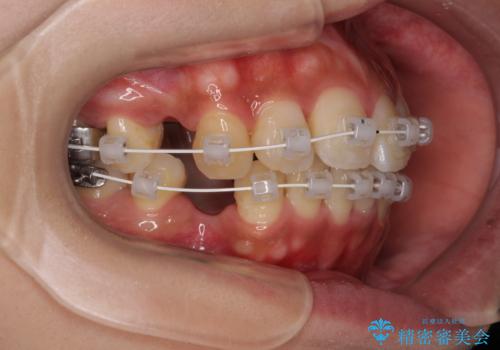

- 前歯の突出感とデコボコを気にして来院された患者様です。

奥歯の噛み合わせをみると、上顎歯列が全体的に前突している状態であり、この咬み合わせのまま歯列を整えると出っ歯になってしまう可能性がありました。

アンカースクリューと補助装置を使用して上顎大臼歯を遠心移動させることで咬み合わせを改善し、更には口元の突出感を改善するために上下左右の小臼歯4本を抜歯し、ワイヤー装置によりデコボコを解消しながら口元の突出感も改善していくこととしました。